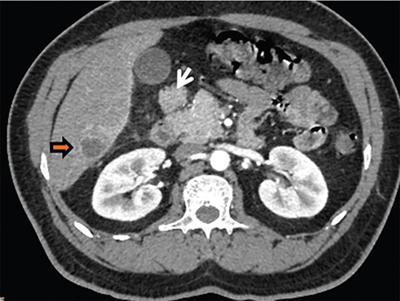

Image

Axial CT image shows pancreatic tissue (arrows) completely encircling the second part of the duodenum in patient with extramural annular pancreas.